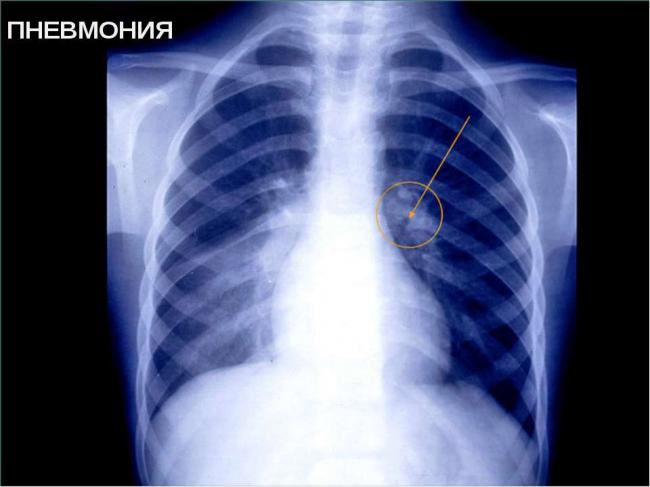

Незаменимым для постановки точного диагноза пневмонии является рентгенография грудной клетки. Она проводится в прямой, а при необходимости и в боковой проекции и позволяет не только установить диагноз острой пневмонии и выявить возможные осложнения, но и оценить эффективность лечения.

- Лучевая диагностика. Чтобы определить воспаление легких у взрослых, проводится такое обследование, как рентгеноскопия. Считается, что его результаты являются основополагающими в постановке диагноза, поскольку на снимке хорошо видно зону воспалительного процесса. Назначаться может и компьютерная томография легких.